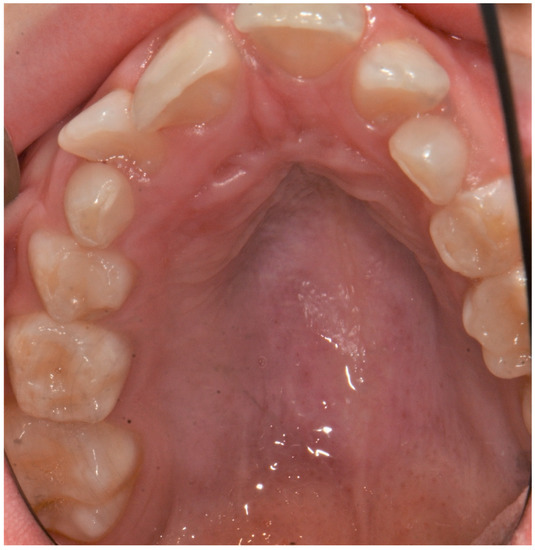

| Present study 2021 | 1 patient | M | high narrow palate, crowding, molar incisor hypomineralization (MIH), second class | 9 |